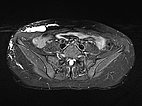

Die transversale, T2-gewichtete, fettunterdrückte MRT auf Höhe der Beckenschaufel zeigt die Ausdehnung der LM auch im Bereich der rechten Flanke. Nur die epifaszialen Anteile der Bauch- und Rumpfwand sind betroffen.

Die transversale, T1-gewichtete, fettunterdrückte MRT nach Kontrastmittelgabe zeigt nur ein minimales Enhancement der dünnen Wände der lymphatischen Malformation. Dies ist typisch für eine LM.